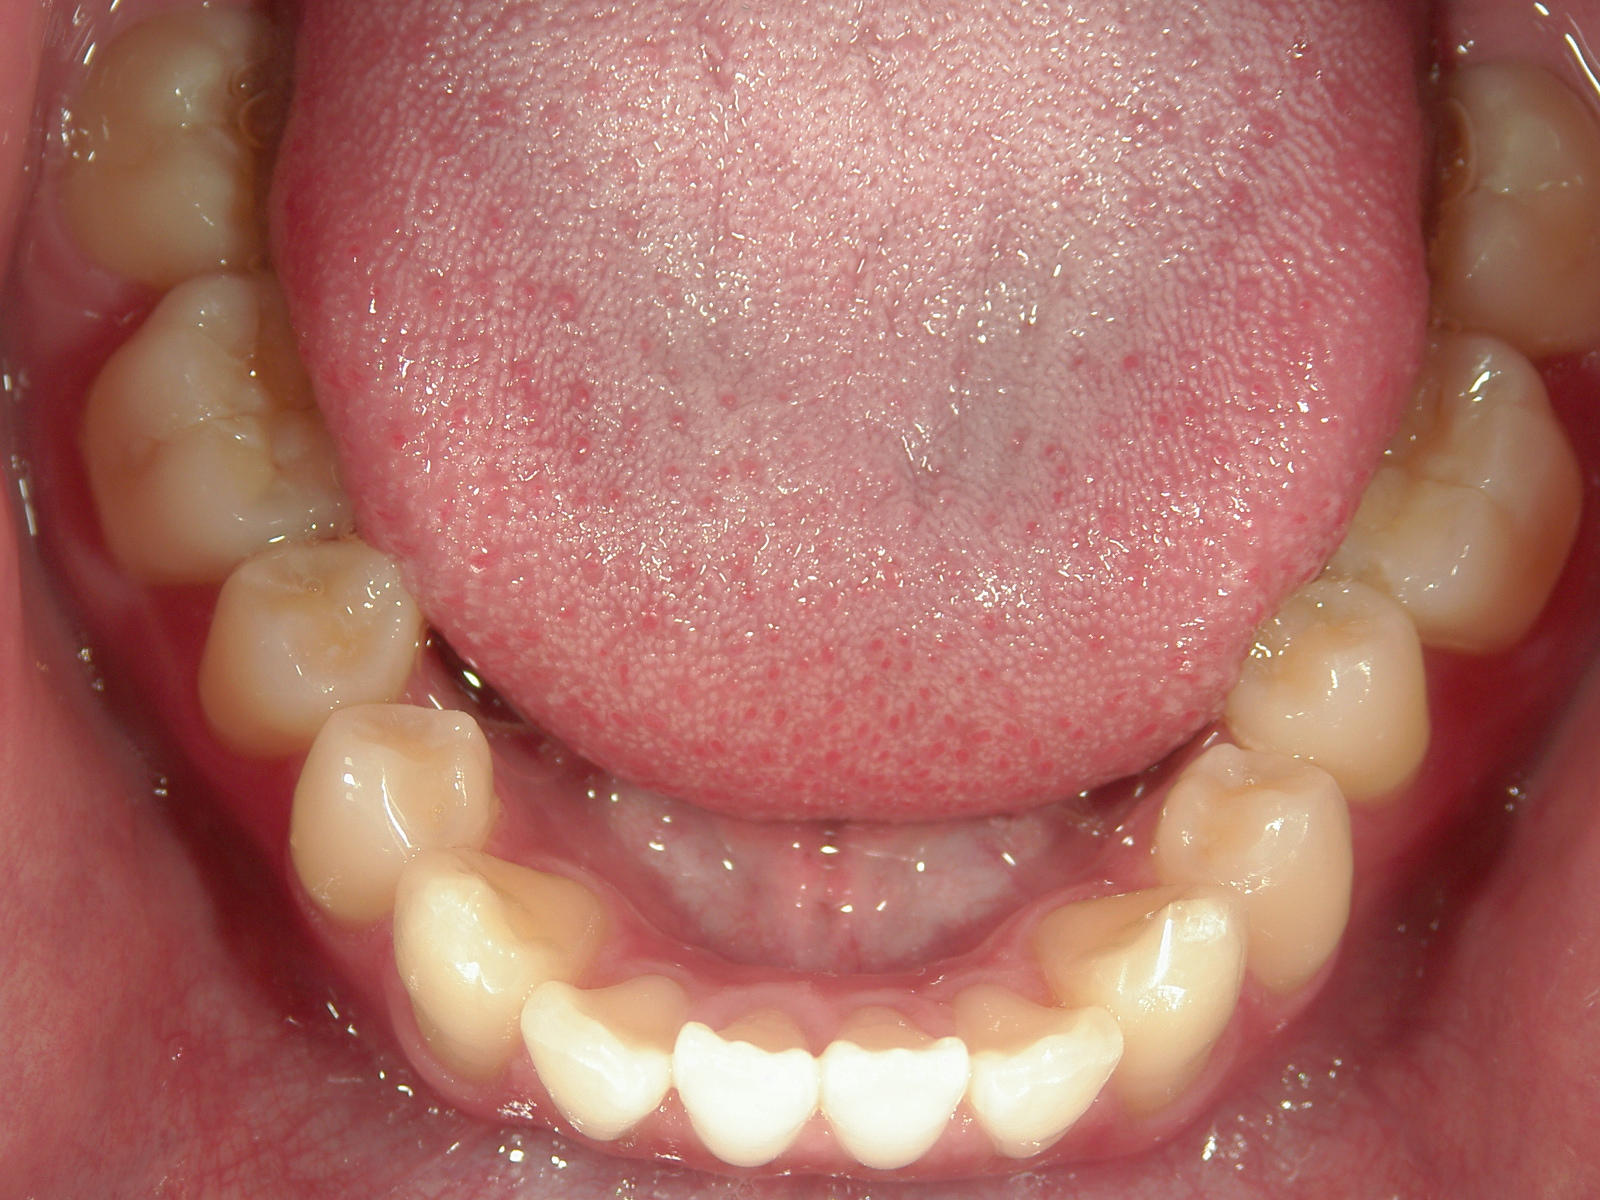

インビザライン矯正 症例(24)

主訴: 前歯の隙間が気になる。

カテゴリー : 隙間がある(空隙歯列)